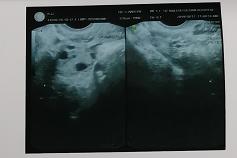

经过长时间的思想斗争后,小翠最终决定来到玛莉亚进行人流手术。手术之前小翠照例进行B超检查,可B超提示没有发现胚胎,只显示宫腔内有呈粗点状策划,这个结果让医生和小翠都有些出乎意料,于是B超医生立即与赵淑萍医生进行会诊,怀疑小翠是葡萄胎的可能,决定先进行手术处理。